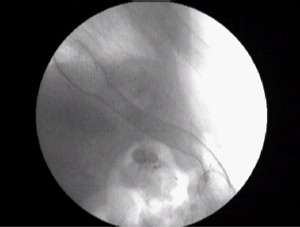

His gastroscopy was done and the scope could not be negotiated across tha anstomosis.The wire could not be passed under fluoroscopy for dilatation with another gastroenterologist .

I could pass a wire and dilate the esophago-jejunal anastomosis with placement of a covered metallic self expandeble stent for palliation of dysphagia with half of the covered stent in the j-shaped jejunum and half proximally.